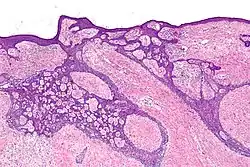

Nodular basal-cell carcinoma

.jpg)

Nodular basal-cell carcinoma (also known as "classic basal-cell carcinoma") accounts for 50% of all BCC.[29] It most commonly occurs on the sun-exposed areas of the head and neck.[30]: 748 [31]: 646 Histopathology shows aggregates of basaloid cells with well-defined borders, showing a peripheral palisading of cells and one or more typical clefts.[29] Such clefts are caused by shrinkage of mucin during tissue fixation and staining.[32] Central necrosis with eosinophilic, granular features may also be present, as well as mucin. The heavy aggregates of mucin determine a cystic structure. Calcification may also be present, especially in long-standing lesions.[29] Mitotic activity is usually not so evident, but a high mitotic rate may be present in more aggressive lesions.[29] Adenoidal BCC can be classified as a variant of NBCC, characterized by basaloid cells with a reticulated configuration extending into the dermis.[29]